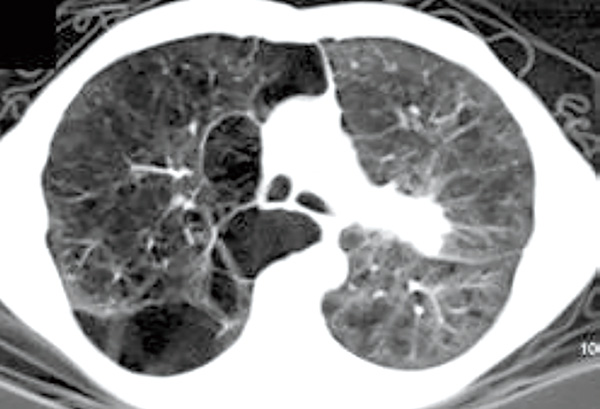

为了评估肺气肿在免疫治疗的COPD合并晚期NSCLC患者中的预后作用,该项研究纳入了2013~2024年ICI单药一线或二线治疗的、COPD(经肺功能测定)合并晚期NSCLC患者,根据胸部CT视觉发现的肺气肿将患者进行分类。

结果显示,研究共包括111例COPD合并肺癌的患者,其中77例合并肺气肿。与无肺气肿患者相比,COPD合并肺气肿患者的OS显著延长(17.3个月 vs. 8.5个月,P=0.008),无进展生存期(PFS)也呈临界的改善趋势(3.3个月 vs. 2.4个月,P=0.641)。多因素分析显示,肺气肿仍然是更长OS的独立因素(HR=0.49,95%CI 0.30~0.81)。不良事件发生率在不同肺气肿状态之间无显著差异(P=0.455)。